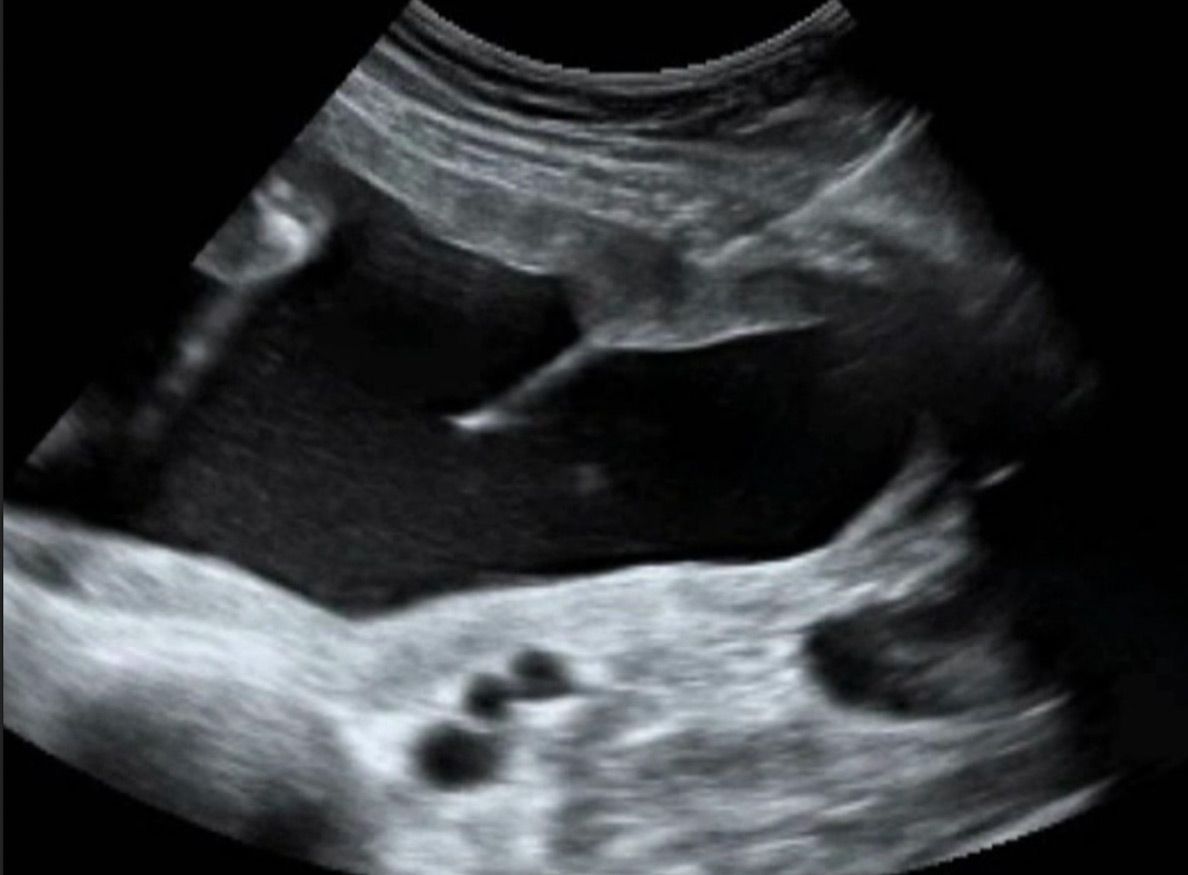

Fruchtwasserpunktion

Die Punktion erfolgt im Untersuchungszimmer. Zunächst die Bauchhaut desinfiziert und ein steriles Tuch über die Beine gelegt. Mit der Nadel wird dann die Fruchthöhle punktiert. Der Untersucher verfolgt den Verlauf der Nadel mittels Ultraschall und kann auf diese Weise die korrekte Position der Nadel bestätigen. Nach korrekter Platzierung der Nadel, wird etwa 15ml Fruchtwasser entnommen. Dieses wird innerhalb von 24 Stunden wieder nachgebildet.

Die gesamte Punktion dauert etwa eine Minute, und wird von den meisten Patientinnen als nicht schmerzhaft beschrieben. Das Fruchtwasser wird an Humangenetik zur weiteren Diagnostik weitergeleitet. Abschließend erfolgt nochmals eine Ultraschallkontrolle.